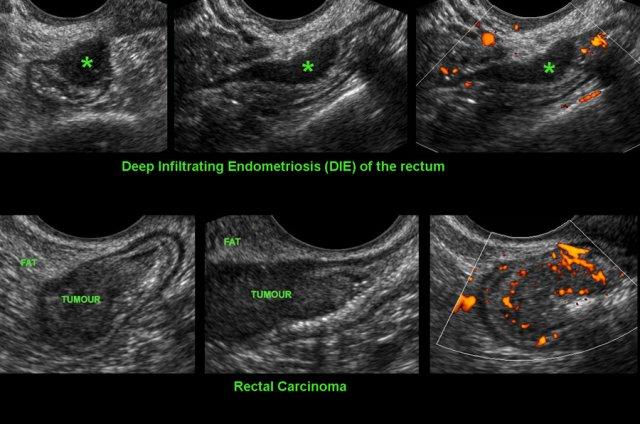

Phân biệt DIE với ung thư biểu mô

Phân biệt ung thư trực tràng với DIE tại trực tràng.

Cả hai bệnh lý đều biểu hiện là các khối đặc, bờ tương đối rõ, giảm âm vừa phải, khu trú không đối xứng xuất phát từ trực tràng với xu hướng làm hẹp lòng ruột. TVUS có thể là chìa khóa để phân biệt hai bệnh lý này.

Trong DIE, khối giảm âm kém mạch máu, khu trú ở bờ ngoài của trực tràng và liên tục với lớp cơ giảm âm. Lớp dưới niêm mạc và niêm mạc đại tràng còn nguyên vẹn.

Trong ung thư trực tràng, khối giảm âm giàu mạch máu và khối xuất phát từ niêm mạc, với mất cấu trúc lớp khu trú là hậu quả của sự phát triển khối u xuyên thành.